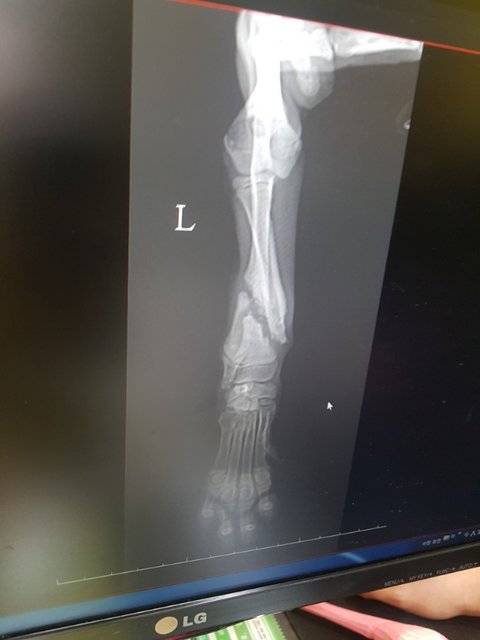

보호소 입소때부터 앞다리를 들고 있었고 조금씩 딛고 있는 모습에 설마 골절은 아니꺼라 생각했습니다.

앞다리는 골절 거기다 코로나에 걸렸습니다.